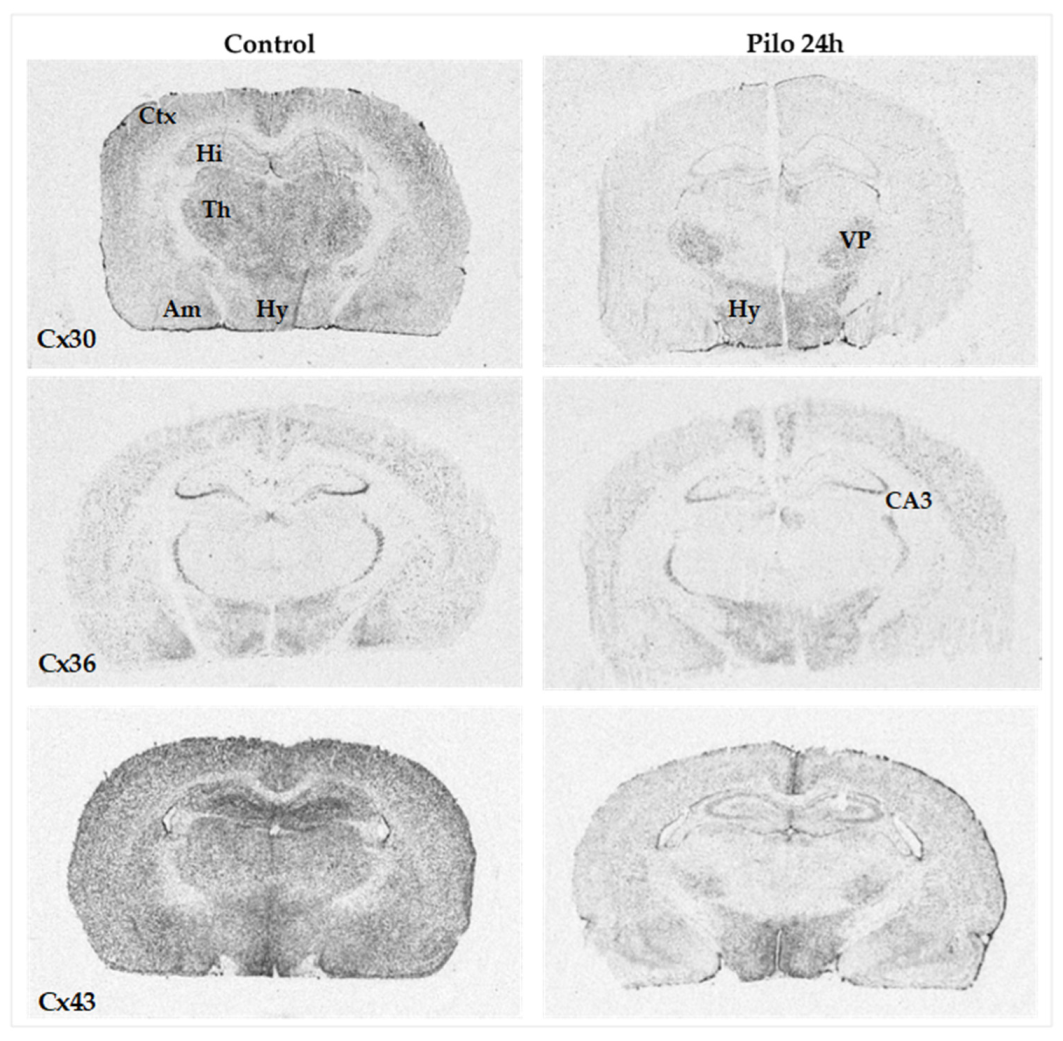

2.1. Cx mRNA Expression